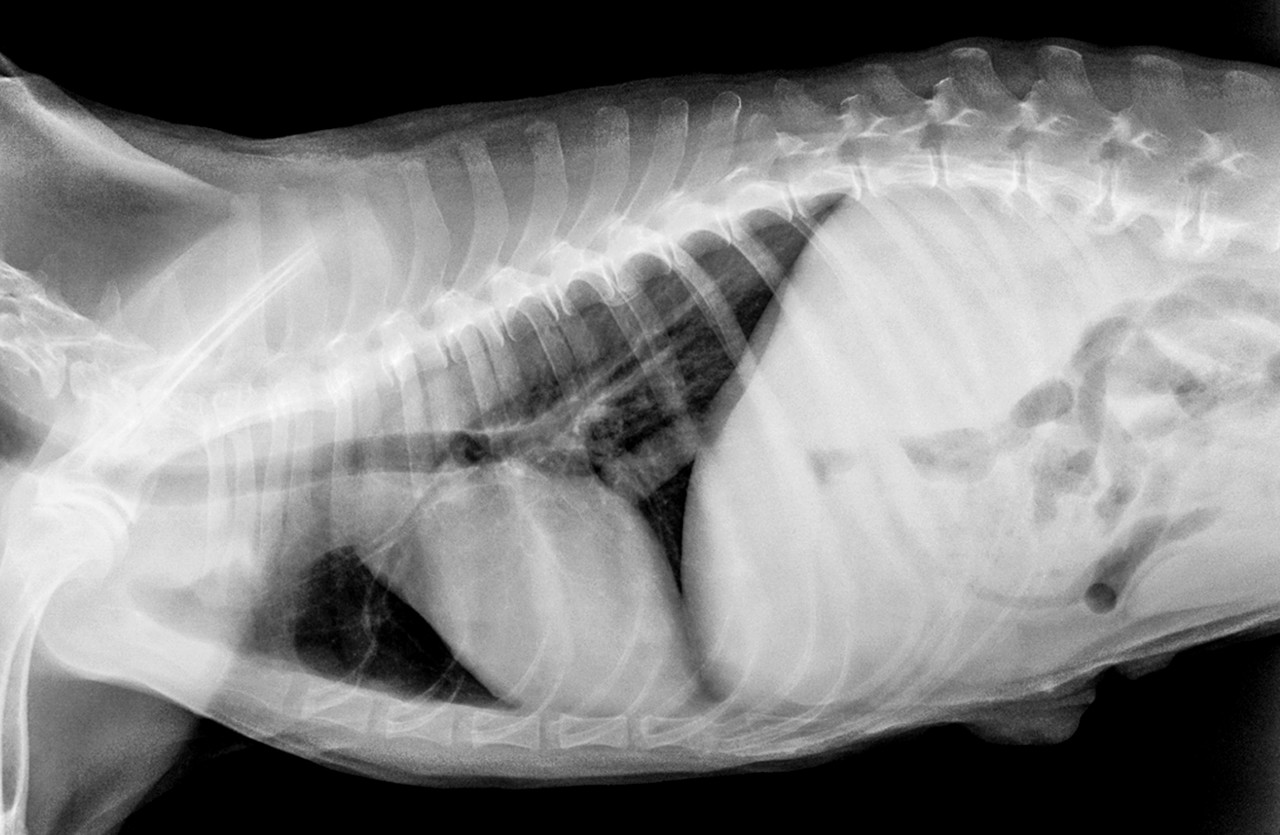

흉강경

폐나 심장 등 흉강내 기관에 발생한 질환을 최소침습수술을 통해 치료합니다.

최소 절개 후 흉강경을 삽입하여 정밀한 수술이 진행됩니다.

개흉술에 비하여 통증 및 출혈이 적고 빠른 회복과 일상 복귀가 가능합니다.

유미흉 수술, 심낭막 절제술, 임파선 절제술, 흉강내 조직검사